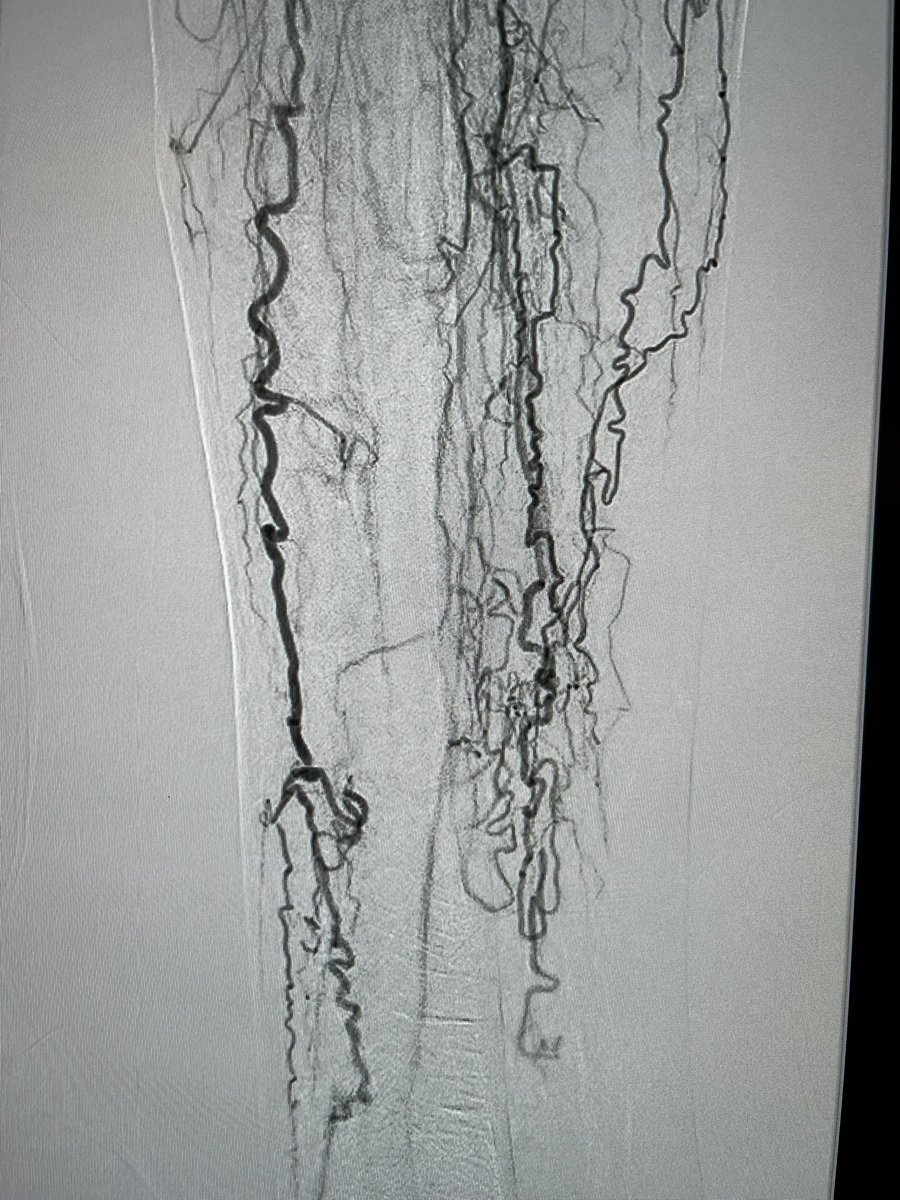

We completed the first 2 perc bypass in Illinois w #Detour @endologix Excited for this groundbreaking technology to be in the hands of #limbsalvage docs around the globe. @ShawnPenn33 @DeanFerreraDO @Abd_Alrifai @MarcoShaker @tlevin @advocatehealth

3

4

13